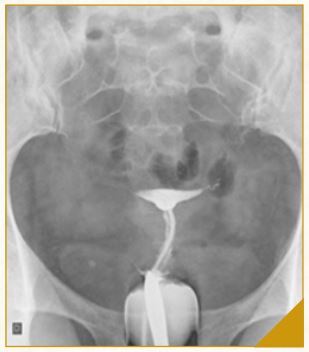

USG-TV e Histerossalpingografia

3. Prova Cotte negativa bilat ou trompas impervias na HSG

Indicar VDL